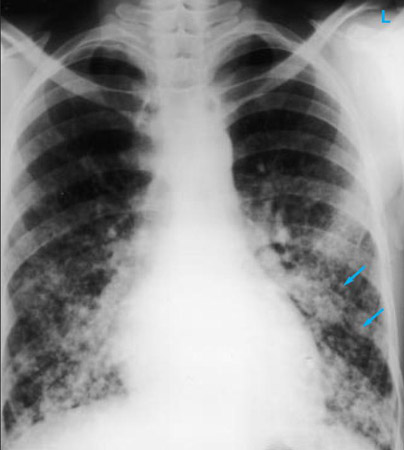

Radiografía de tórax que muestra múltiples metástasis pulmonares miliares (flechas). El tumor primario fue un carcinoma de tiroides

E. Dick, Student BMJ. 2001;9:10-12